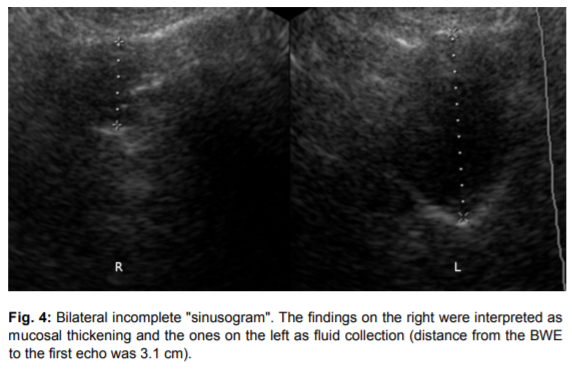

좌측그림: 비대된 점막의 우측 부비동, 우측그림: 물이 찬 좌측 부비동

부비동염 (축농증)에서는

부비동의 경계선이 보일 수 있고

점막의 비대나

새까맣게 물이 찬 것이 보입니다.

3) BWE (Back Wall Echo)

X축(time scale)에서 4-6cm 떨어져

나타나는 back wall echo로,

삼출액이 1-3ml(평균 2ml)이상 저류되면

BWE가 나타납니다.